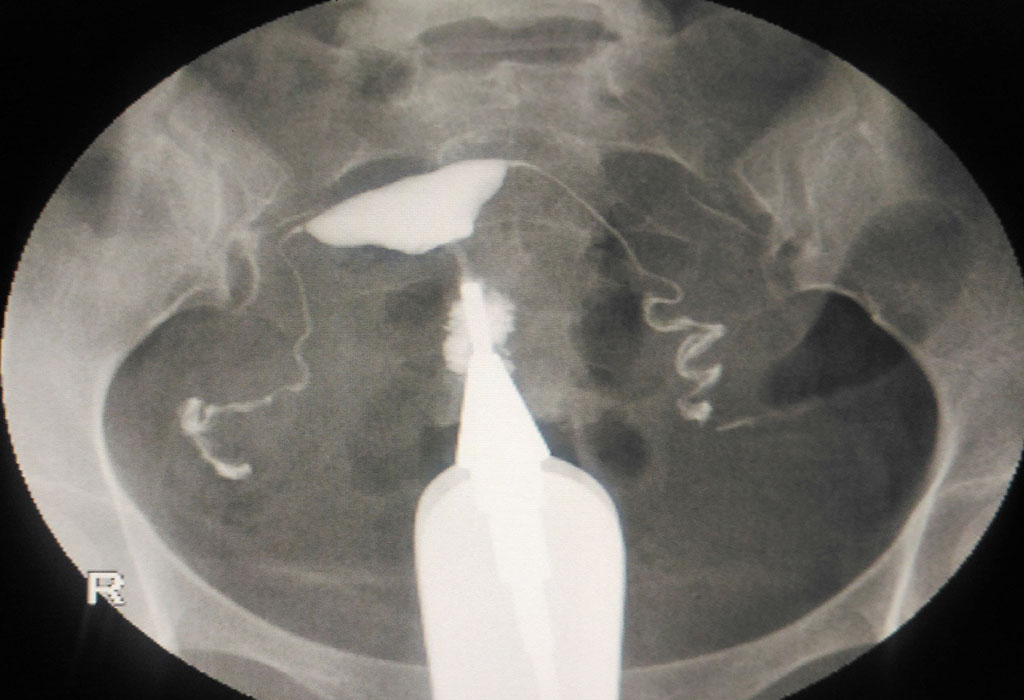

Hsg Testing Procedure . the hsg (hysterosalpingogram) procedure helps the doctor determine if the fallopian tubes are open or blocked. Learn how to prepare, what to. — a hysterosalpingogram (hsg) is a radiographic diagnostic test that examines the uterus and fallopian tubes of. — hsg test is a diagnostic test to evaluate the health of a woman's reproductive system, especially the fallopian tubes and uterus. hsg is a fluoroscopic exam that uses contrast material to check for blockages or abnormalities in the uterus and fallopian tubes. — an hsg test checks your uterus and fallopian tubes for blockages or scarring that could prevent conception. Learn when to do it, what.

— hsg test is a diagnostic test to evaluate the health of a woman's reproductive system, especially the fallopian tubes and uterus. Learn when to do it, what. hsg is a fluoroscopic exam that uses contrast material to check for blockages or abnormalities in the uterus and fallopian tubes. — a hysterosalpingogram (hsg) is a radiographic diagnostic test that examines the uterus and fallopian tubes of. Learn how to prepare, what to. the hsg (hysterosalpingogram) procedure helps the doctor determine if the fallopian tubes are open or blocked. — an hsg test checks your uterus and fallopian tubes for blockages or scarring that could prevent conception.

Hsg Testing Procedure Learn how to prepare, what to. — a hysterosalpingogram (hsg) is a radiographic diagnostic test that examines the uterus and fallopian tubes of. the hsg (hysterosalpingogram) procedure helps the doctor determine if the fallopian tubes are open or blocked. — hsg test is a diagnostic test to evaluate the health of a woman's reproductive system, especially the fallopian tubes and uterus. — an hsg test checks your uterus and fallopian tubes for blockages or scarring that could prevent conception. Learn how to prepare, what to. hsg is a fluoroscopic exam that uses contrast material to check for blockages or abnormalities in the uterus and fallopian tubes. Learn when to do it, what.